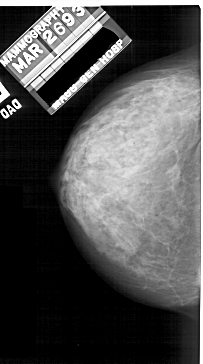

A_1912_1.LEFT_CC

LEFT_CC LINES 5086 PIXELS_PER_LINE 2836 BITS_PER_PIXEL 12 RESOLUTION 43.5 NON_OVERLAY